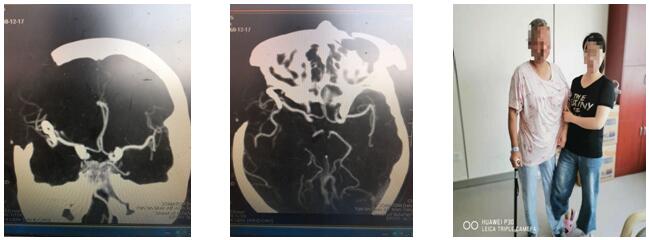

此時患者已經陷入深昏迷,情況緊急,時間就是生命,已經沒有再多的時間考慮了,科主任劉小雷、責任總醫(yī)師游文良再次組織全科醫(yī)師討論,詳細向家人告知目前情況,最終決定急診開顱手術。如何避免術中發(fā)生大出血,成為擺在神經外科二病區(qū)團隊面前的最大問題。劉小雷主任,游文良責任總醫(yī)師帶領的神經外科團隊經過慎重、反復討論,決定由翼點入路夾閉動脈瘤并清除血腫。手術在全麻下進行。首先要通過腦自然間隙找到大腦中動脈下干,仔細分離,暴露動脈瘤,予以夾閉。整個過程都必須經過腦自然間隙進入顱腦深部,保證腦組織、血管和神經的完好,最后清除血腫,血腫腔嚴密止血。手術圓滿完成。目前患者處于恢復期,患者神志清,言語流利,思維清楚,除左側肢體肌力稍減弱外,其他功能均正常,在家人攙扶下可以慢慢行走。

近年來,延安大學咸陽醫(yī)院神經外科二病區(qū)劉小雷主任,游文良責任總醫(yī)師帶領的神經外科團隊一直致力于顯微血管手術,神經外科顯微手術,微創(chuàng)手術的開展。目前延安大學咸陽醫(yī)院神經外科顯微血管外科手術技術已達咸陽市先進水平,此例手術的圓滿完成,標志著我院神經外科顯微外科手術技術踏入新的高度,將更好地為咸陽市及周邊縣區(qū)人民服務。